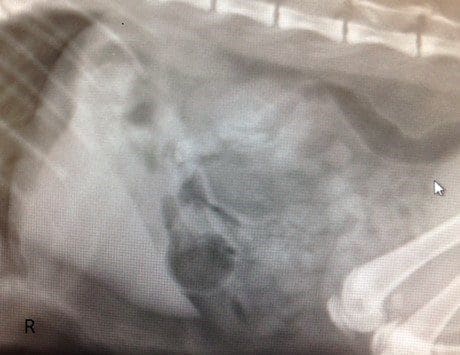

The following abdominal radiographs and abdominal ultrasounds were performed to investigate the cause of the acute vomiting.

Figure 1: Right lateral abdominal radiograph showing gaseous distension of the pyloric antrum